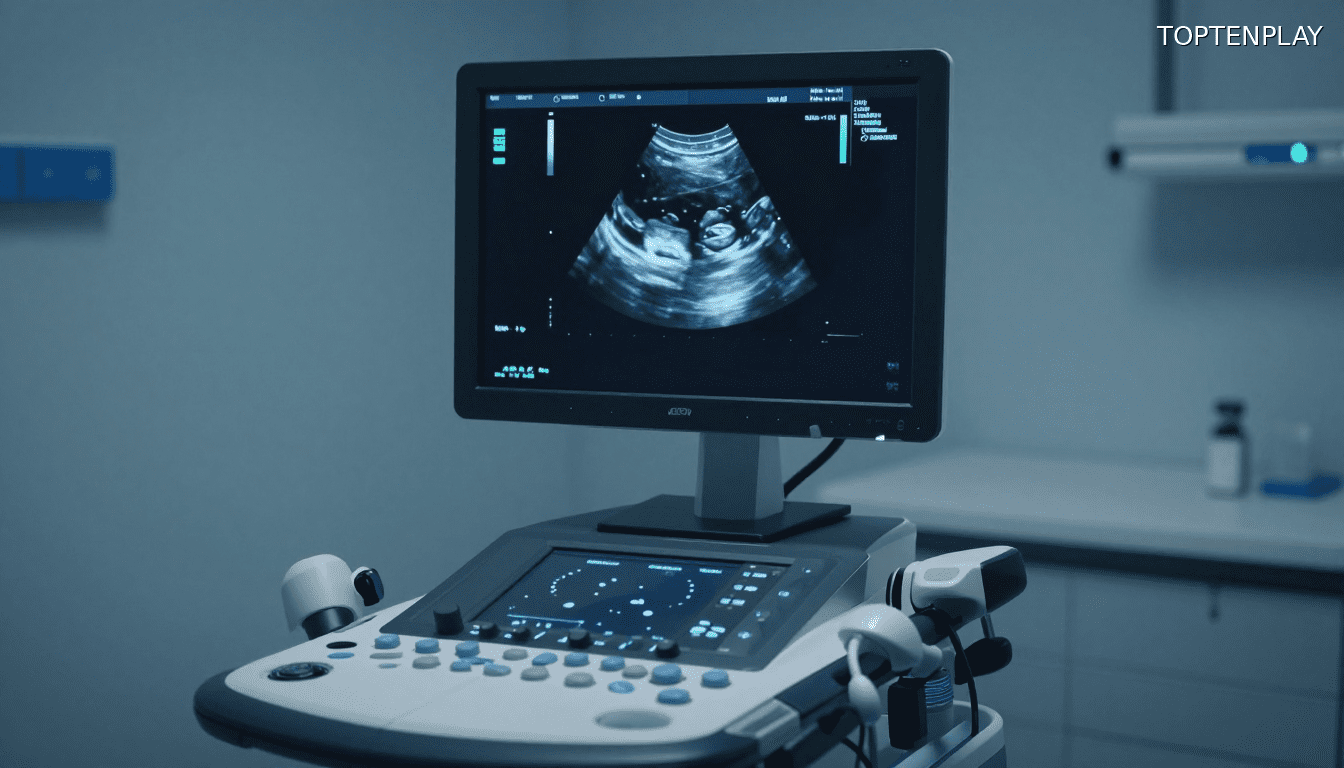

Les images médicales révèlent une réalité sidérante : Suze est bel et bien enceinte, mais son utérus est vide. Le fœtus ne se trouve pas où il devrait être.

« Un kyste ovarien bénin géant de plus de 9 kilos occupait une place considérable dans l’abdomen, et derrière lui se trouvait un bébé presque à terme », explique le Dr John Ozimek, directeur médical du service d’obstétrique. L’enfant s’est développé dans la cavité abdominale, à proximité du foie, complètement masqué par la masse tumorale.

Cette configuration anatomique explique pourquoi personne n’avait rien détecté. Le kyste géant a agi comme un écran parfait, rendant la grossesse totalement invisible aux examens classiques. Aucune échographie, aucun signe physique évident. Juste cette tumeur connue qui grossissait, cachant en réalité une vie en formation.